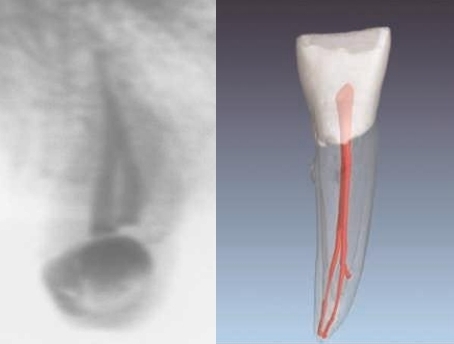

Bayonet root image. From trauma. Can lead to necrotic pulp from intrapulp pressure increase